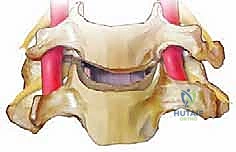

الخطوة 6: زراعة الطعم العظمي (Bone Graft Insertion)

بعد إزالة القرص، تتبقى فجوة بين الفقرتين. لمنع انهيار هذه المسافة ولتحفيز التحام الفقرتين معاً، يتم إدخال "طعم عظمي" أو قفص صناعي (Cage) مصنوع من مادة PEEK أو التيتانيوم ومملوء بمادة عظمية.